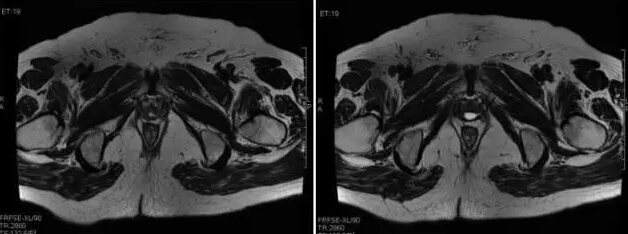

张争教授:实际上,该患者术后3个月时尿控尚未恢复,复查PSA升至0.137 ng/ml;术后6个月时尿控基本恢复,复查PSA升至0.257 ng/ml;术后7个月时尿控完全恢复,复查PSA升至0.328 ng/ml。确诊为生化复发。紧接着术后复查盆腔MRI:无局部复发,骨扫描未见骨转移,腹部CT及胸片未发现转移(图2)。患者随后接受了挽救性放疗+长期的内分泌治疗(长期全阻断),治疗3个月时PSA降至0.06 ng/ml,持续内分泌治疗,PSA逐渐上升,在随访至22个月时PSA升至1.247 ng/ml。

图2. 术后复查MRI表现

☆专家解读(七):王霄英教授解读术后复查MRI并就相关问题讨论